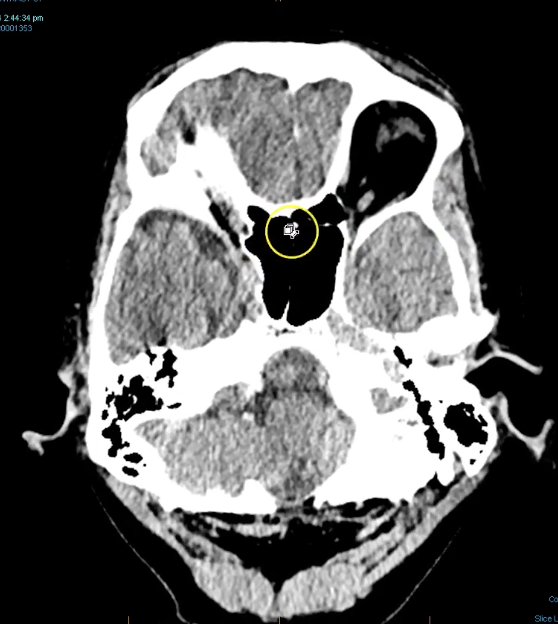

New cards

term image

third ventricles